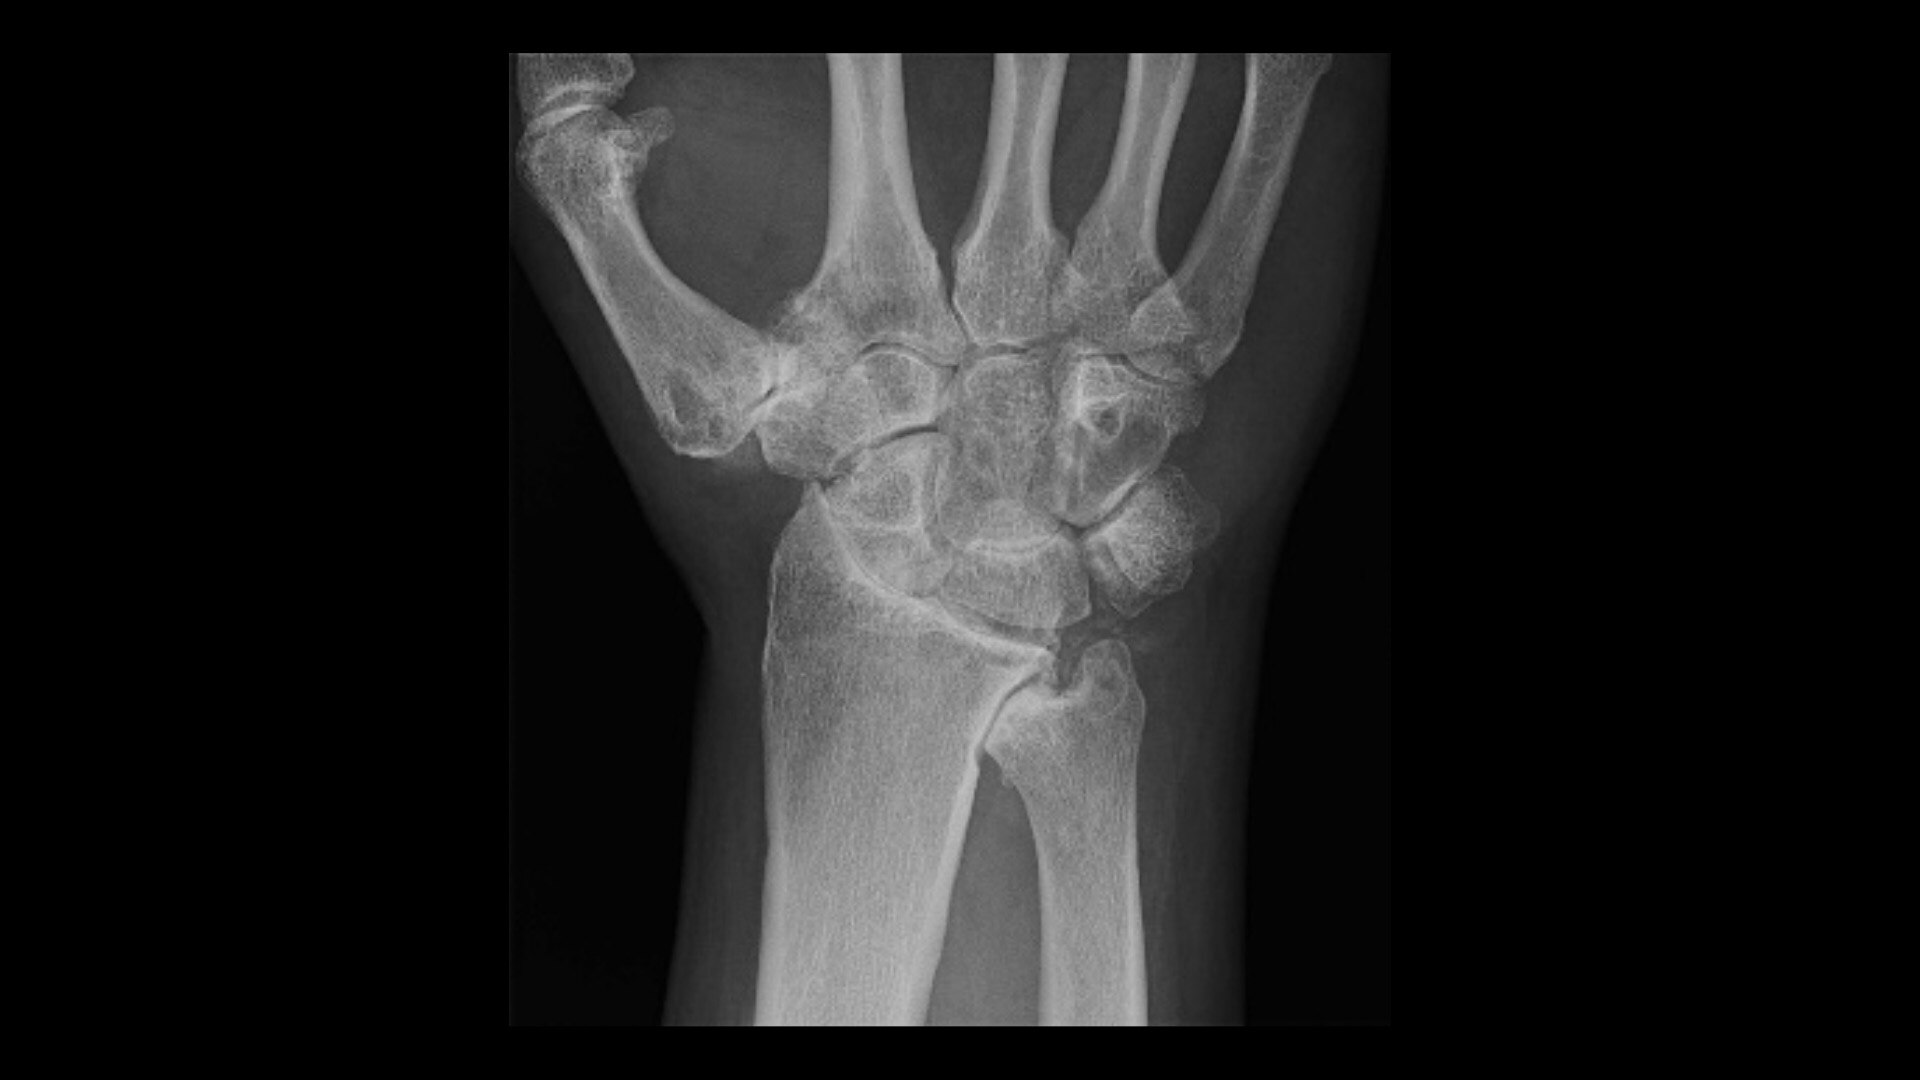

Scegli le innovazioni più recenti per migliorare la qualità delle immagini e ridurre la dose e gli artefatti. Oltre alle applicazioni Ricostruzione e IQ, il pacchetto base fornisce anche il software di sistema TC più recente e consente all'hardware² e alle soluzioni di automatizzare la selezione del protocollo TC.